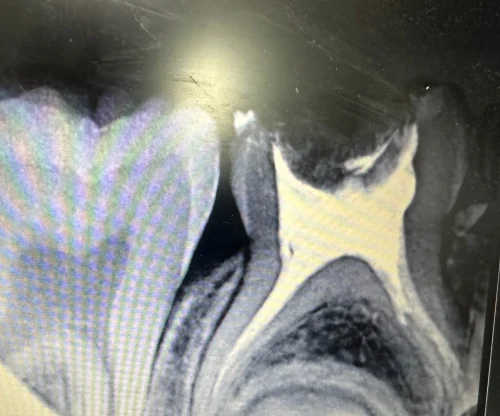

A clinical assessment presented a severely decayed primary mandibular molar #T with percussion tenderness. The radiograph of IOPAR reveals pulp involvement with furcation radiolucency, an irreversible pulpitis. The family chose Magnum Clinic because of its expertise in children's dentistry, considering that it emphasizes painless dental procedures for children

Diagnosis: Periapical in Tooth T- Irreversible Pulpitis: Which means the nerve inside the tooth is badly inflamed and the infection has reached the tip of the root. It will not heal on its own.

The pulp was extirpated, the canals dried out and were shaped with pediatric rotary files, and they were then profusely irrigated. The canals were then dried off carefully and filled with Metapex obturating paste, which safely resorbs with time.

An artificial Biolex crown of pre-made shape was cemented to the tooth: this guaranteed safety, reduction of chewing, and durability. The whole process took place during two sessions, which were about 45 minutes.